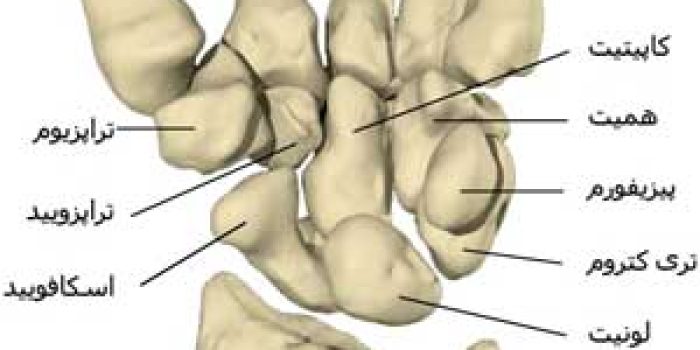

مچ دست یا کارپوس (Carpus) از هشت استخوان تشکیل شده است، که به آنها استخوانهای کارپ (Carpal bones) میگویند. استخوانهای کارپ در دو ردیف قرار دارند. ردیفی که نزدیک به استخوانهای ساعد قرار دارند، به آن ردیف بالایی یا پرگزیمال (Proximal row) اطلاق میشود، و ردیفی که نزدیک به استخوانهای کف دست قرار دارند، به آن ردیف پایینی یا دیستال (Distal row) میگویند.

در ردیف پرگزیمال، چهار استخوانچه وجود دارد که به ترتیب از طرف شست به سمت انگشت کوچک عبارتند از اسکافوئید (Scaphoid)، لونات (Lunate)، تریکوتروم (Triquetrum) و پیزیفورم (Pisiform). در ردیف دیستال نیز چهار استخوانچه قرار دارد که به ترتیب از طرف شست به سمت انگشت کوچک عبارتند از تراپزیوم (Trapezium)، تراپزوئید (Trapezoid)، کاپیتیت (Capitate) و همیت (Hamate). استخوانهای کارپ در کنار هم قرار گرفتهاند و یک قوس را تشکیل میدهند. این قوس به سمت قدام یا کف دست خم میشود.